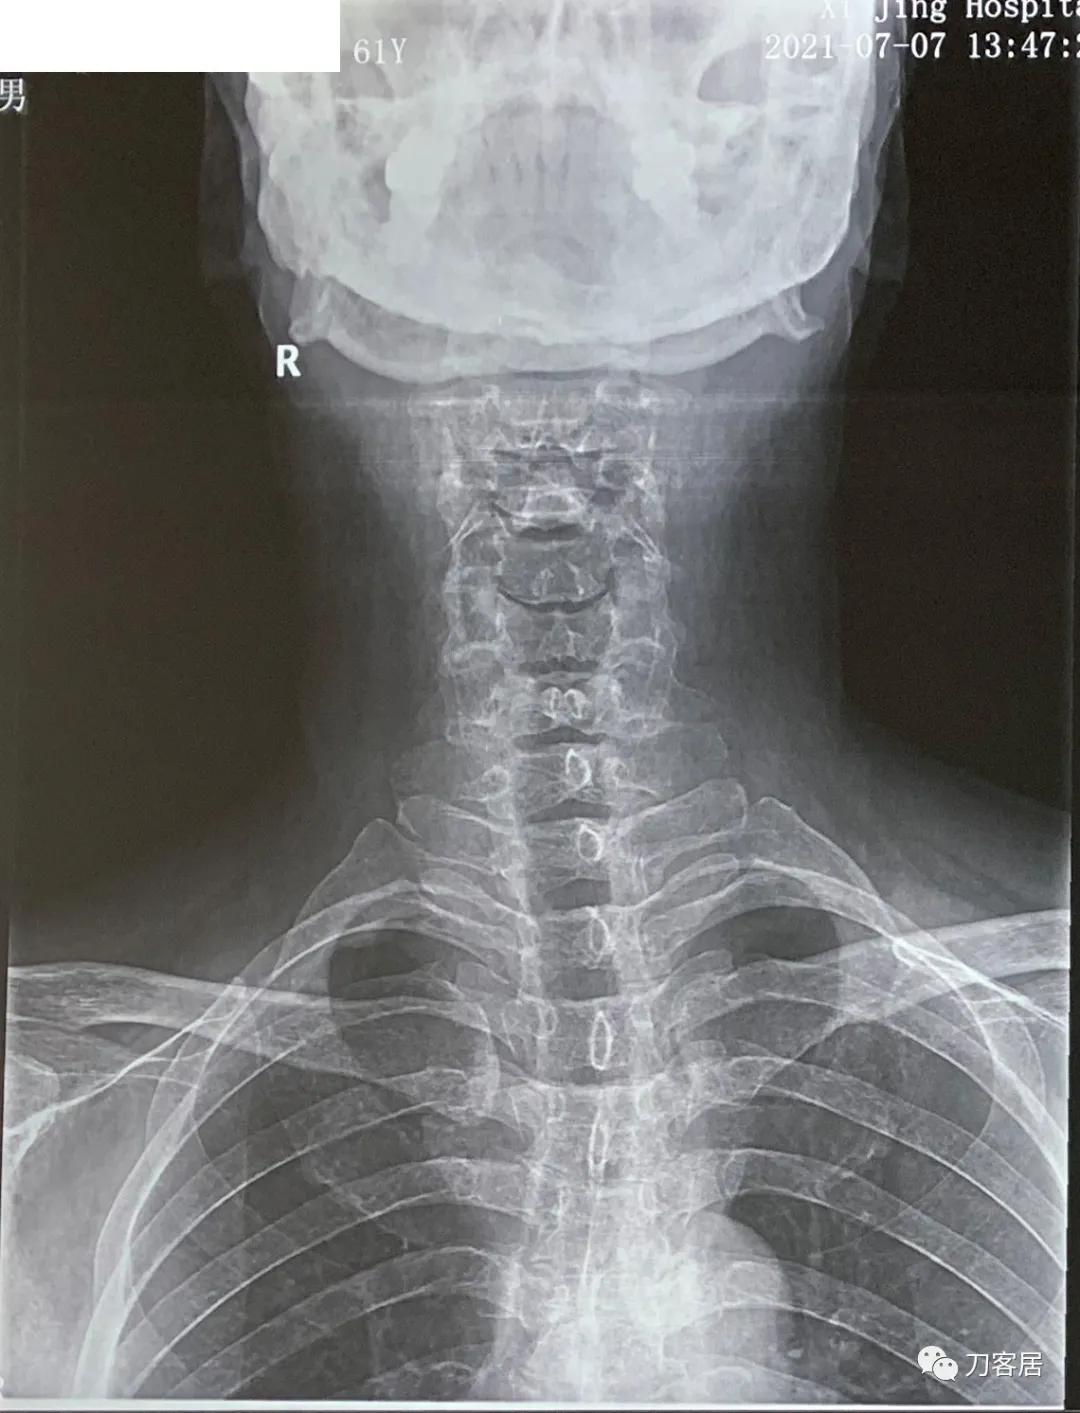

图7. 20210721颈椎正位X线片,颈椎未见大问题, 但胸椎可能有侧位,颈胸交界处疑似侧弯,但患者并无次主诉痛苦,所以,没有做进一步的检查。